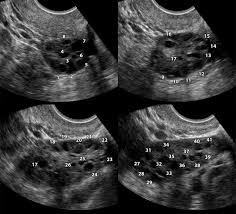

يلجأ للمركز العديد من النساء للتلخص من هذه الظاهرة التي تلازم النساء العربيات اكثر من غيرهن، تتلخص اعراض هذه الظاهرة في عدم انتظام الدورة الشهرية او انقطاعها، ارتفاع نسبة هرمون الذكورة (Testosterone) الذي يؤدي الى ظهور بثور الوجه Acne وتزايد نمو الشعر في الوجه، البطن، الصدر والارجل، افراط في السمنة وسقوط شعر الرأس، قلة تحسسهن لهرمون الانسولين واخيراً صعوبة في الانجاب.

نقوم في المركز بإجراء الفحوصات الهرمونية اللازمة ومعالجة كافة الظواهر الاخرى مع التشديد على فقدان الوزن واعطاء الادوية الخاصة لتنظيم الدورة وتحسين الاباضة بالاضافة الى معالجة مشكلة الانجاب بالطريقة السالفة الذكر وهي تقنية انضاج البويضات خارج الجسم (IVM).